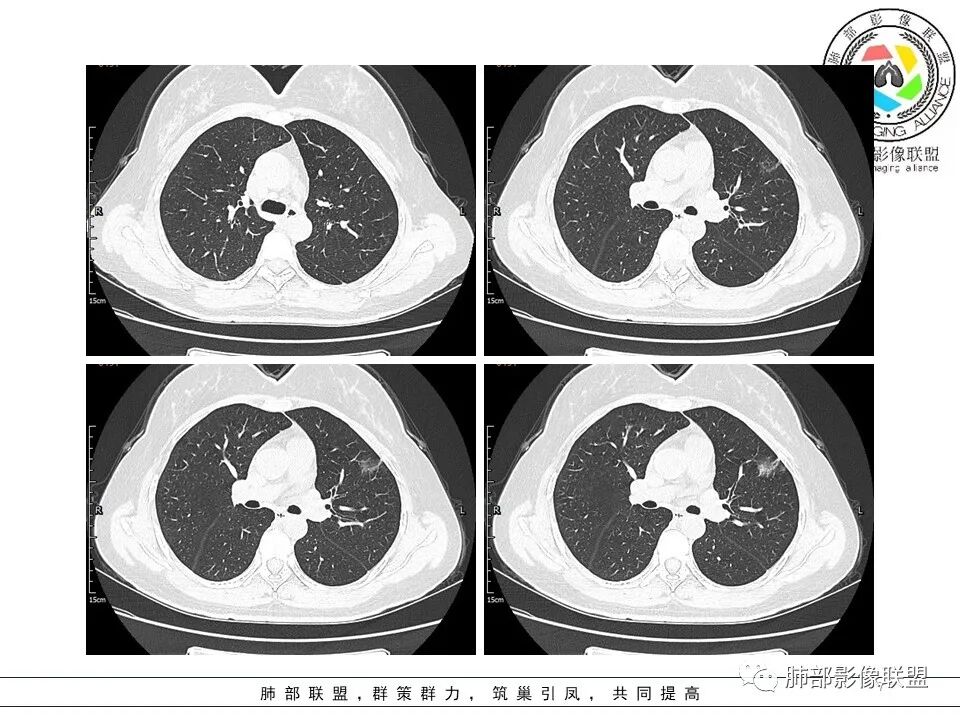

二.关于胸膜下小结节:

结节影太小,尚未能够充分反映出影像学特征。随访观察应当是恰当的处置方式。